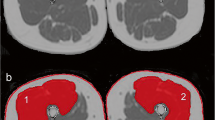

The assumption that a ring-shaped actuator will generate planar waves, which are necessary for 2D MRE (Bishop et al. 2000), has previously been shown to be valid (Klatt et al. 2010), and additionally assumptions of muscle as a linearly viscoelastic, incompressible, locally homogeneous solid (Manduca et al. 2001) were applied. Phase accumulations of greater than ± 2π were corrected using a Laplacian-based phase unwrapping algorithm (Barnhill et al. 2015). The data were then imported to MATLAB, and a custom pipeline (Barnhill et al. 2016) was used to calculate the magnitude of the complex modulus, |G*|. Regions of interest (ROIs) corresponding to the four main quadriceps muscles (i.e. vastus lateralis (VL), rectus femoris (RF), vastus intermedius (VI), vastus medialis (VM)), combined quadriceps muscle, combined hamstrings and adductors and whole thigh (quadriceps, hamstrings and adductors) were manually segmented using ImageJ software (Fig. 3). In areas bordering subcutaneous fat, ROIs were drawn conservatively to reduce the contribution from partial volume effects.

Example anatomy, MRE and fat fraction images from an older and young participant. Cod liver oil capsule denoting the mid-femur point is visible on the anterior surface of the thigh. ROI regions are overlaid on the anatomical image. Quadriceps ROI is represented by black dotted line incorporating RF, VI, VL and VM muscle groups. Whole-thigh ROI includes both quadriceps and hamstrings and adductors ROI. Fat fraction pixel values are scaled from 0 to 50% to aid visualization

Fat fraction was calculated from the signal intensity of the OP (TE 2.46 ms and 4.92 ms) and IP (TE = 8.61 ms) images as described in (Lee and Yu 2014) for the same ROIs as MRE. CSA was also calculated for the same individual muscle groups, quadriceps, hamstrings and adductors and whole thigh as the MRE and fat fraction measurements. The cross-sectional area of the muscle was quantified on each image by drawing a region of interest around the muscle using ImageJ software. For CSA determination, the muscle was traced accurately around the whole perimeter including in areas adjacent to subcutaneous fat. Classification of sarcopenia status of the whole thigh of the older muscles was based on muscle size criteria (Janssen et al. 2002).

Muscle CSA showed a similar direction of change to the stiffness measurements, in that mean CSA was lower in the older compared to the younger group over all measured ROIs (Table 1). The reduction was significant for VM (8.42 ± 2.71 vs 17.96 ± 4.66 cm2, p = 0.003), quadriceps (49.76 ± 12.99 vs 73.91 ± 8.62 cm2, p = 0.001), hamstrings and adductors (54.28 ± 10.41 vs 76.97 ± 12.42 cm2, p = 0.008) and over the whole thigh (104.03 ± 21.55 vs 150.88 ± 20.46 cm2, p = 0.003, Fig. 4c). Based on CSA of the whole thigh, all the older participants were sarcopenic with 3/6 (50%) of the older adult group fulfilling the criteria for class II sarcopenia (i.e. < 2 SD below mean CSA of the young adults) and the remaining participants exhibiting class I sarcopenia (i.e. < 1 SD below mean CSA of the young adults) (Janssen et al. 2002).